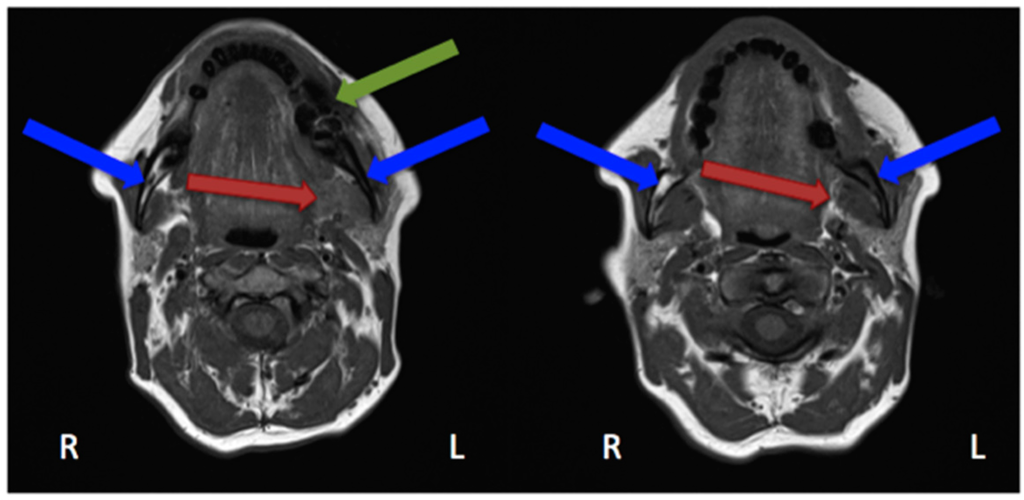

In the study by Guggenberger et al., all MRONJ foci “showed markedly decreased signal on T1-with increased signal on T2-weighted images” [29]. This was the case for all except one patient, in whom an intermediate signal on T2 was seen. “Contrast uptake of affected bone and surrounding tissue was noted in all patients and foci of BONJ” [29]. Furthermore, the authors described that contrast-enhanced MR imaging shows more extensive changes in comparison with the clinical examination and CBCT imaging [29]. In their study, Stockmann et al. stated that “MRI has a high detectability for BONJ lesions” [18] but limitations were found concerning the extent of the detection [18]. Bedogni et al. assessed in their study 11 MRI scans performed on MRONJ patients [42]. Gadolinium (intravenous) was used as a contrast agent. These images showed two patterns of bone disease: “Exposed areas showed a low signal in T1- and T2-weighted and inversion recovery images, which suggests low water content and is histopathologically correlated with paucity in cells and vessels (osteonecrotic pattern). Unexposed diseased bone was characterised by T1 hypointensity and T2 and IR hyperintensity, which suggests high water content and inflammation, associated with hypercellularity, osteogenesis, and hypervascularity (osteomyelitic pattern).” [42]. Hypointensity in T1 was also seen in MRI scans performed on our patient (Figure 6 and Figure 7).

Figure 6.

Magnetic resonance imaging (Siemens, Avanto, 1.5T, Sequence: T1 tse tra) Patient: 48 years old, female, metastatic breast cancer, zoledronic acid for 2 years (panoramic radiograph Figure 1). Green arrow showing the MRONJ necrosis, red arrows showing the oedema, blue arrows showing the differences between the right side: normal fatty bone marrow and left side: signal loss, due to loss of fat. Pair of screenshots. AAMOS staging: stage 2.

Figure 7.

Magnetic resonance imaging (Siemens, Avanto, 1.5T, Sequence: T2 tse tra) Patient: 48 years old, female, metastatic breast cancer, zoledronic acid for 2 years (panoramic radiograph Figure 1). Green arrow showing the MRONJ necrosis: hypointense bone marrow, red arrows showing the oedema. Pair of screenshots. AAMOS staging: stage 2.

Krishnan et al. described early MRI findings of MRONJ in their publication. This includes at the early stage “the loss of the normal T1 hyperintensity of fatty marrow in the mandible and maxilla.” [43] “Bone destruction, soft tissue edema and enhancement, inferior alveolar nerve thickening, and pterygoid muscle swelling and enhancement” [43] are findings of more advanced stages. Exemplary MRI protocols are found in the publications by Bedogni et al., Stockmann et al. or García-Ferrer et al. [18,42,44]. Although MRI scans are very helpful for defining the extent, the 99Tcm-MDP 3-phase bone scan was superior to both CT and MRI [45].